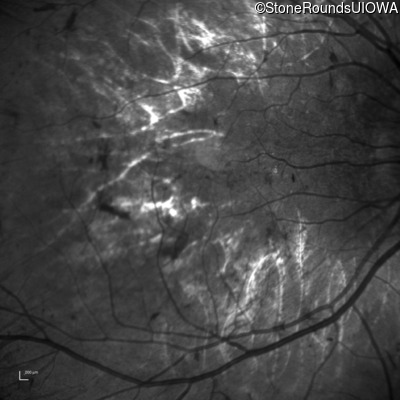

Infrared Fundus Photograph - Left - 5/160

Exemplar